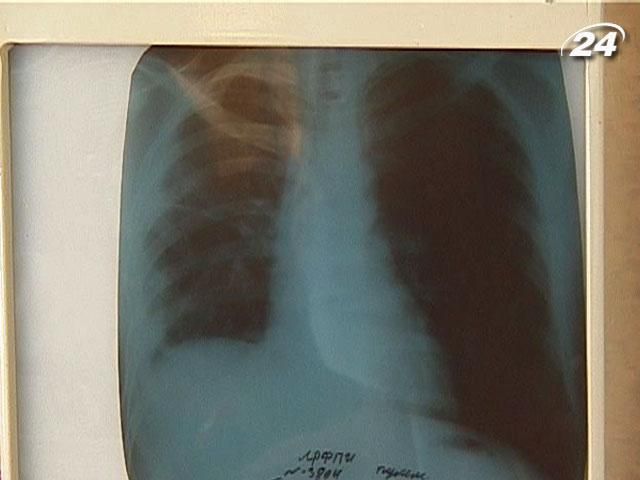

На Донетчине заболеваемость туберкулезом снизилась на 30%

По данным ВОЗ, более 60% больных ВИЧ / СПИДом умирают в Украине именно от туберкулеза. Благодаря объединению усилий фонда Рината Ахметова "Развитие Украины" и местной власти, на Донетчине за 5 лет уровень заболеваемости этой болезнью уменьшился почти на 30%.